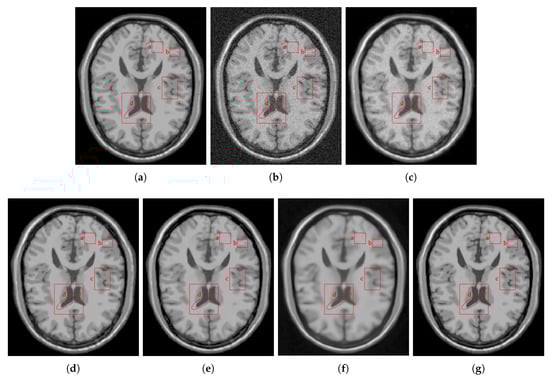

4.2.2. Real Data